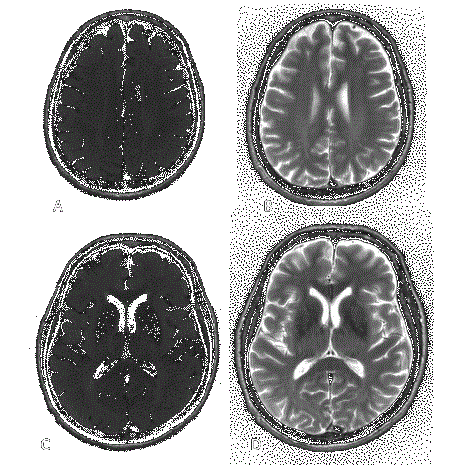

Los estudios de neuroimágen se consideran la herramienta de mayor importancia en el diagnóstico y se recomiendan como tamizaje en pacientes con alto riesgo de desarrollar LMP. 1 Las imágenes típicas se caracterizan por lesiones en la sustancia blanca, subcorticales, de tamaño y localización variable, generalmente multifocales, con predilección frontal y parietooccipital, aunque pueden ocupar virtualmente cualquier área del sistema nervioso central. Se ha reportado involucro de la fosa posterior, especialmente, cerebelo y pedúnculos cerebrales medios (Imagen 3).21 Hay algunas variaciones en las características de las lesiones dependiendo de la causa desencadenante de la LMP. Por medio de tomografía se pueden observar lesiones hipodensas, generalmente sin realce al medio de contraste, (únicamente realzan del 5-10% de los casos).22 La resonancia magnética muestra lesiones hipointensas en T1 e hiperintensas en T2 y FLAIR; quince por ciento de los pacientes con VIH y 40% de los pacientes con LMP por uso de natalizumab presentan realce con gadolinio.23 En los casos secundarios al uso de natalizumab, las lesiones pueden ser únicas. Se han identificado dos patrones inflamatorios; 1) el asociado a síndrome inflamatorio de reconstitución inmunológica (SRI), generalmente fulminante, 2) el asociado a inmunoreacción anti-VJC, el cual confiere buen pronóstico. En pacientes con SRI, las lesiones pueden tornarse edematosas, provocando efecto de masa, con realce al medio de contraste por tomografía y resonancia magnética.24 Dentro de los exámenes de laboratorio, el análisis de líquido cefalorraquídeo para documentar la presencia de VJC por medio de la reacción en cadena de la polimerasa (PCR), siendo este el estudio más importante, ya que confiere una sensibilidad >95% y una especificidad >97%.25 Dado que los portadores asintomáticos de VJC pueden presentar viremias espontáneas, cualquier contaminación del LCR con sangre puede arrojar falsos positivos. Además, un resultado negativo para VJC por PCR no descarta la enfermedad. Esto último cobra especial importancia en pacientes con VIH en tratamiento antirretroviral combinada de alta efectividad (HAART por sus siglas en inglés), ya que al aumentar la cuenta de CD 4, disminuye la carga viral de VJC, lo cual puede dificultar su aislamiento en LCR. En pacientes que desarrollan SRI, es un reto aún más importante, pues además de la dificultad en la identificación virológica, el patrón clásico en imagen presenta algunos cambios ya mencionados.26